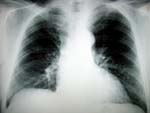

Η αξονική τομογραφία καλύτερη στον εντοπισμό του καρκίνου των πνευμόνων

Ουάσινγκτον: Η εξέταση των πνευμόνων των καπνιστών με αξονική τομογραφία αντί της κοινής ακτινογραφίας επιτρέπει τη μείωση κατά 20% της θνησιμότητας από το καρκίνο των πνευμόνων, σύμφωνα με αμερικανική έρευνα.